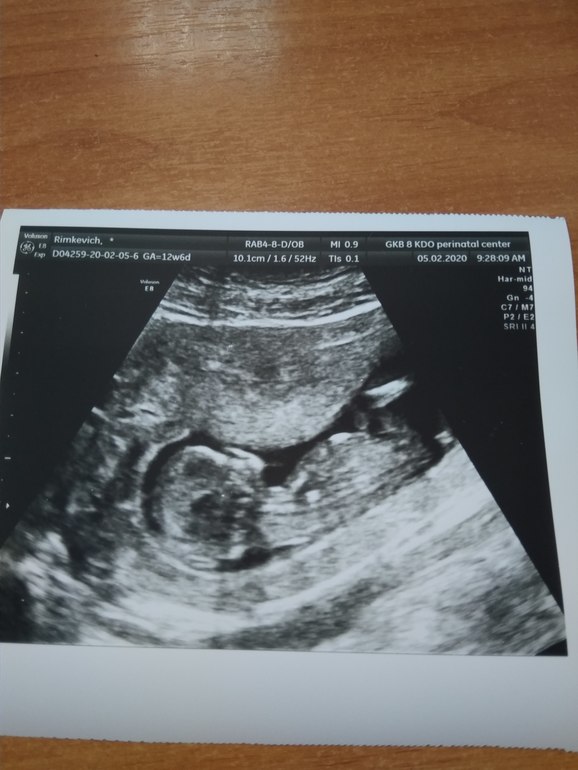

Пол малышаЕсть снимок УЗИ,я слепая мама,не вижу даже намёка на пол, посмотрите свежим взглядом пожалуйста.

Гинеколог меня вчера спросила насчёт пола, говорит все уже на 1 скрининге знают,и мне теперь не живётся спокойно:))

Тут не видно бугорка. На заднем фоне что то виднеется, если это бугорок, то мальчик.

Тут не видно. Но лично я за девочку, уж больно аккуратный малыш у вас. Мальчишки более угловатые что-ли